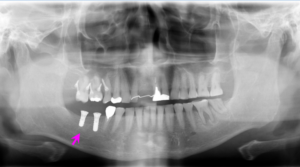

右下インプラント埋入直後のレントゲン写真です。

矢印部に下顎内の神経があり、これを避け、隣の歯と十分距離が保てるような位置でインプラントを埋入できました。